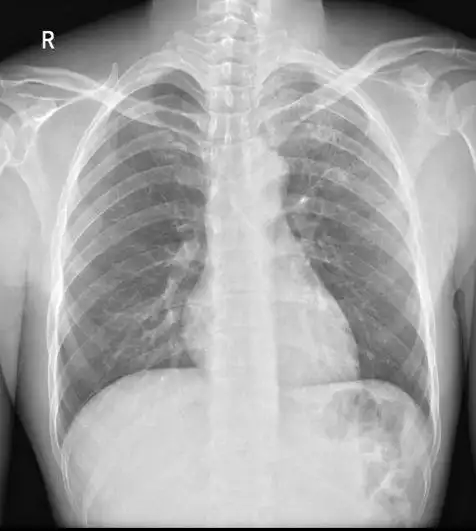

肺结核的影像诊断学习笔记丨影像天地

各型肺结核的典型影像表现

浸润性肺结核